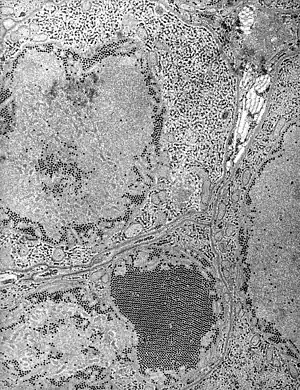

| Electron micrograph of "Saint Louis encephalitis virus" seen in a mosquito salivary gland | |